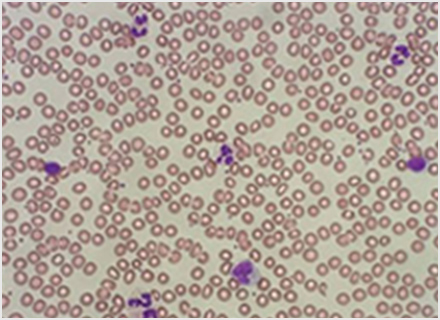

血液は、「赤血球」「白血球」「血小板」の3種類の血球と血しょうからできています。赤血球は酸素を運搬し、白血球は、体内に侵入した細菌やウイルスなどの外敵から体を守る働きをします。血小板は出血を止める働きを、血漿に含まれる凝固因子と呼ばれるタンパク質と共に行っています。血液は骨の中の骨髄と呼ばれる場所で作られます。血液検査はそれらに関わる状態を調べたり、異常を検出することができます。